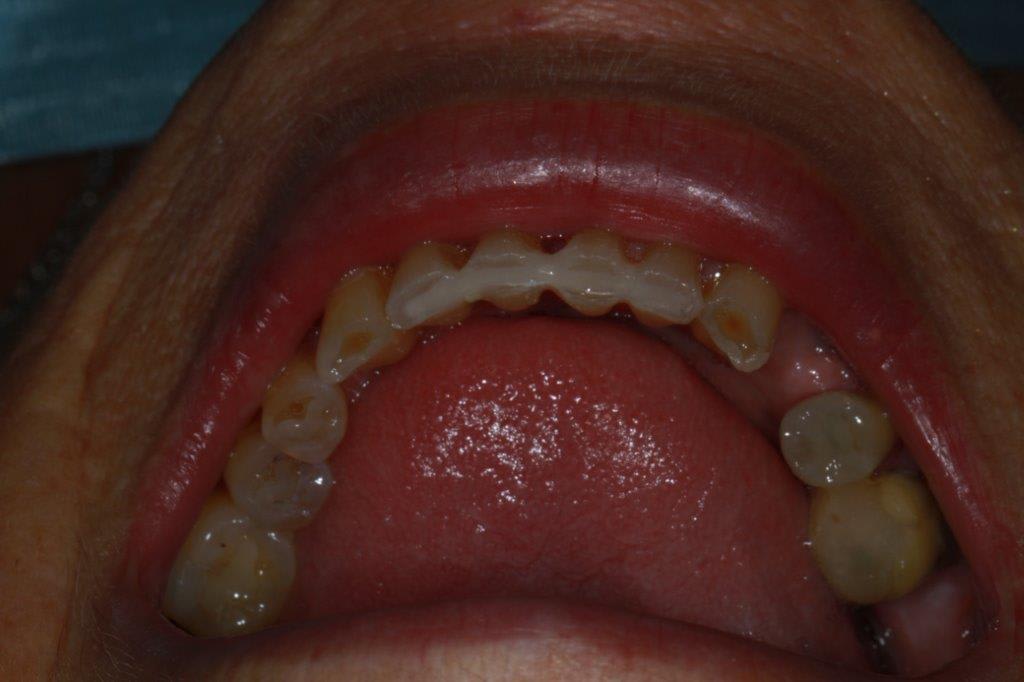

petit cas sympa ancien bridge très mobile....plutôt que d'extraire 25, j'ai déposé la couronne, retraité la dent stabilisation pendant deux mois puis séance d'ostéotension et ce jour pose de deux axioms PX 34120 après expansion...